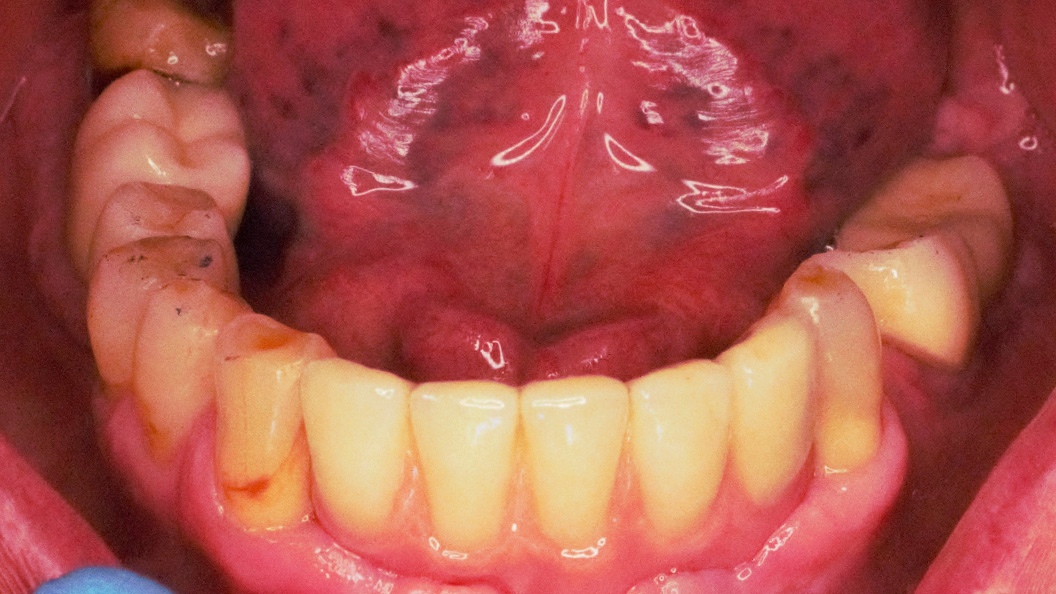

К нам в клинику обратился пациент с жалобой на частично отсутствующие зубы на нижней челюсти.

В ходе лечения были проведены следующие работы:

- санация полости рта;

- установка 3 имплантов системы Alpha Bio;

- изготовление и установка металлокерамических коронок на имлантах системы Alpha Bio.